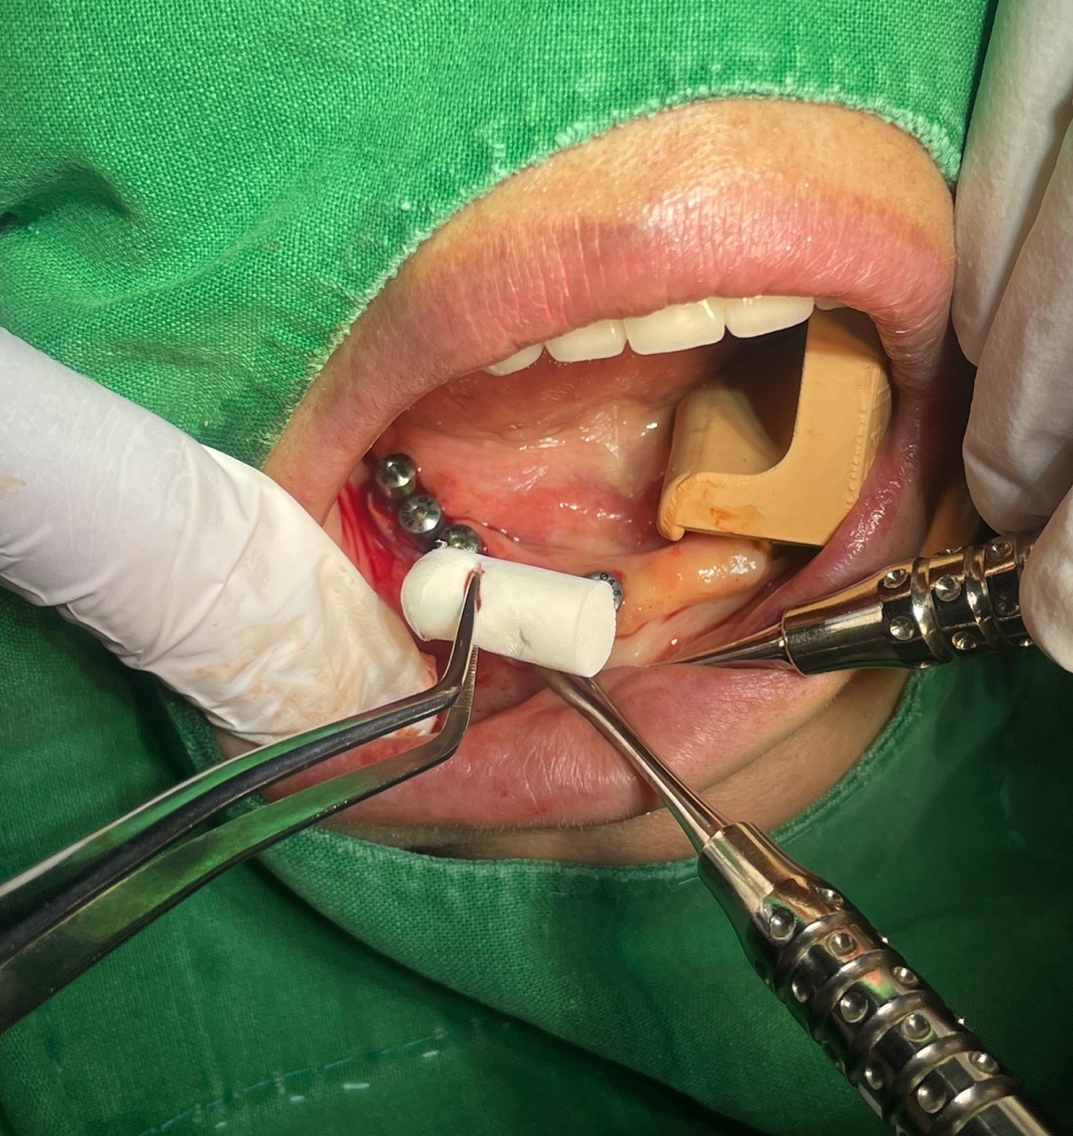

오늘 제가 수술한 환자분은 기존 타치과에서 쓰시던 임플란트 고정성 틀니의 만족도도 나쁘지 않았으나 나이가 아직 50대 후반으로 한창이신 여성 환자분이라 심미적인 이유로 고정성 치아를 원하셨고

제가 CT를 찍고 환자분께 일주일만 시간을 주시면 일주일뒤에는 예쁜 고정성 치아로 만들어 드린다고 자신있게 약속을 드린 환자분이었습니다.

심지어 임플란트를 단 4개만 심더라도 고정성으로 해드릴려고 노력하고 있습니다. 환자분이 느끼시는 만족도가 너무 차이가 납니다. 예전에는 교합력만으로 그 만족도를 가늠할려고 하였지만 그 와는 별개로 틀니를 빼고 있는 밤시간에 느끼는 무치악 스트레스도 무시 못하는 요인이라고 생각이 됩니다.

당장 비용 문제로 크게 고민 되시는 분이 아니라면 웬만하면 하악에서는 특히 고정성 치료를 권해 드리고 있습니다. 그리고 비용도 아예 일정금액으로 고정 시키고 심는 갯수는 제가 최대한 많이 식립해 드릴려고 하고 있습니다.

하악 무치악 환자분께는 어떠한 형태의 고정성 보철물의 디자인이 가능합니다.